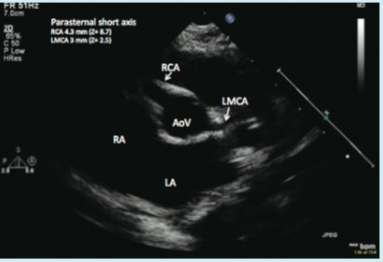

These two case reports describe infants with cardiac and gastrointestinal malformations.